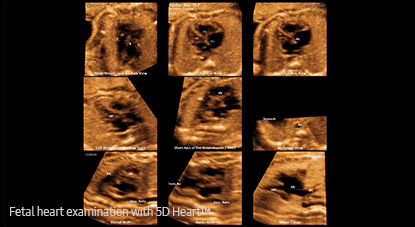

5D Heart

Examen rápido del corazón del feto con 9 planos estándar

La función proporciona 9 planos estándar del corazón mediante el uso de los datos de STIC fetal, así como información importante sobre el desarrollo del corazón del feto de una manera fácil y precisa de acuerdo con la directriz de AIUM.

• 9 vistas estándar del corazón fetal con 5D Heart Color

9 vistas estándar del corazón fetal con 5D Heart Color